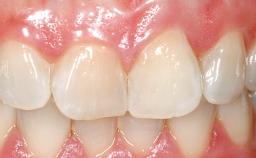

A 30-year-old female patient had lost tooth 21 and was referred to our clinic for consultation and treatment. Due to advanced apical infection, tooth 21 had been extracted two months earlier at another clinic and an acrylic-resin tooth had been bonded to the adjacent teeth. The patient desired implant treatment to avoid any damage to the adjacent natural teeth. While the patient had no history of any systemic disorder, she was a heavy smoker and exhibited medium to advanced periodontitis in the entire jaw. After the initial treatment to achieve a pocket probing depth of less than 4 mm and no bleeding on probing, a decrease in the height of the papillae mesial and distal to the extraction site and overall gingival recession were observed.

Abutment Type CAD/CAM

Prosthesis Type FDP

SAC Level Complex

Defining Characteristics One missing tooth to be replaced by an implant-borne crown